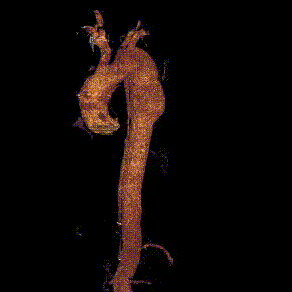

术前CTA:主动脉弓、左锁骨下动脉、胸主动脉附壁血栓伴部分穿透性溃疡。病变位于左锁骨下动脉根部前壁位置,近端锚定区不足

术前CTA三维重建

术前CTA横截面

术前CTA:B型主动脉夹层破裂,左侧胸腔大量积血、积液,双肾萎缩